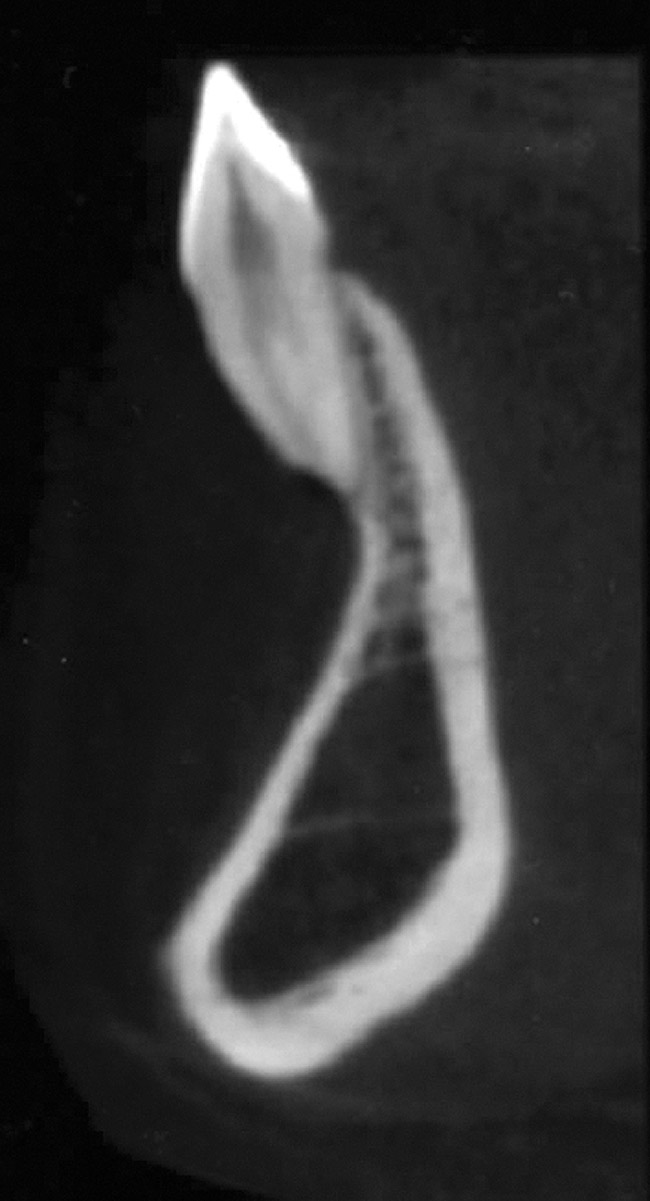

In cases with thin lingual bone, as measured on CBCT (<2.5 mm at a level of 8 mm apical to the CEJ), orthodontic treatment is not advisable, leaving surgical root coverage as the only option. However, the prognosis for this procedure is poorer, because the predominant cause is not addressed. Figure 4 shows the frontal clinical view of a patient with a hyperdivergent growth pattern who presented with post-orthodontic GR of a labially displaced lower central incisor. The sagittal CBCT view (Figure 5) shows complete absence of lingual bone, which contraindicated orthodontic tooth repositioning.

Fig 5. CBCT sagittal view of the same patient showing thin/no bone on the lingual aspect.

Figure 5

Fig 18. CBCT sagittal view shows no bone on the labial aspect and 2.5 mm bone thickness on the lingual aspect.

Figure 18